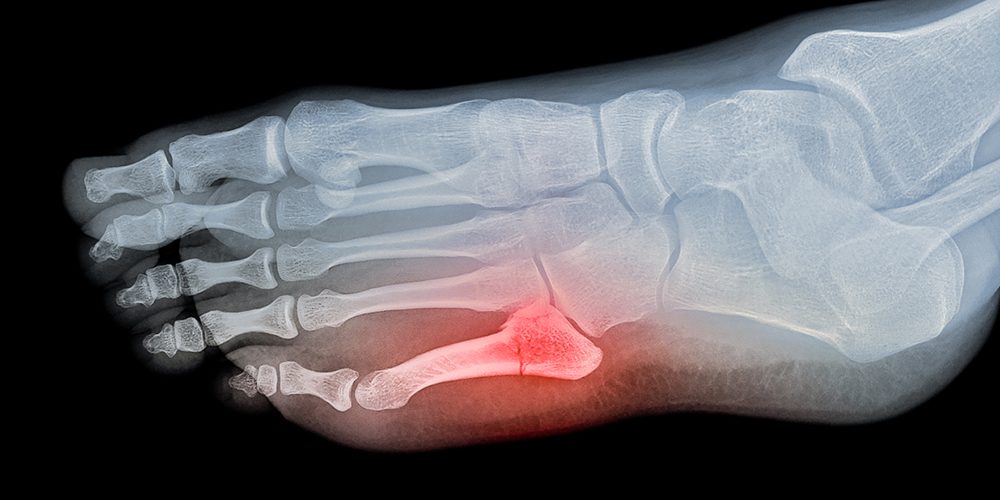

- Serious foot problems (infections, bone and joint pain)

Sinne this article is part of our foot pain series, I don’t want to leave foot care untouched. Common complications of diabetic neuropathy include ulcers, sores that don’t heal and even amputation in some cases. The good news is that you can prevent most of these problems. And besides having a foot exam annually, here are some things that you can do at home yourself: